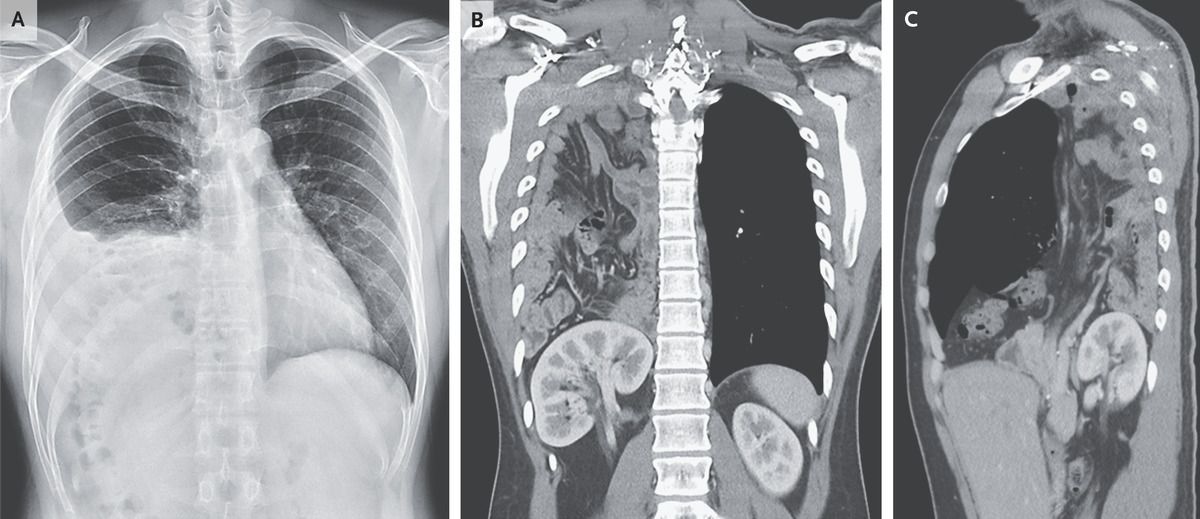

A 25-year-old man was referred to the emergency department owing to abnormal results on a chest radiograph obtained during a preemployment examination. He had no known medical history and no symptoms. His respiratory rate was 14 breaths per minute, and his oxygen saturation was 100% while he was breathing ambient air. On examination, there were decreased breath sounds at the base of the right lung. The abdomen was not tender. A radiograph of the chest showed a possible right pleural effusion, elevated right hemidiaphragm, and suspected translocation of the colon into the right upper quadrant of the abdomen (Panel A). Computed tomography of the chest with the use of contrast material revealed herniation of the right kidney, omentum, and small and large intestines into the right thoracic cavity through a large posterolateral diaphragmatic defect (Panel B shows the coronal view, and Panel C the sagittal view). There were no signs of bowel obstruction. A diagnosis of congenital diaphragmatic hernia due to a posterolateral diaphragmatic defect — also called a Bochdalek hernia — was made. Bochdalek hernia is typically diagnosed in infants and children, who present with respiratory distress. In rare cases, the hernia may remain asymptomatic until adulthood, at which time complications of bowel strangulation or obstruction may occur. The patient declined surgical repair of the diaphragmatic defect and was subsequently lost to follow-up.